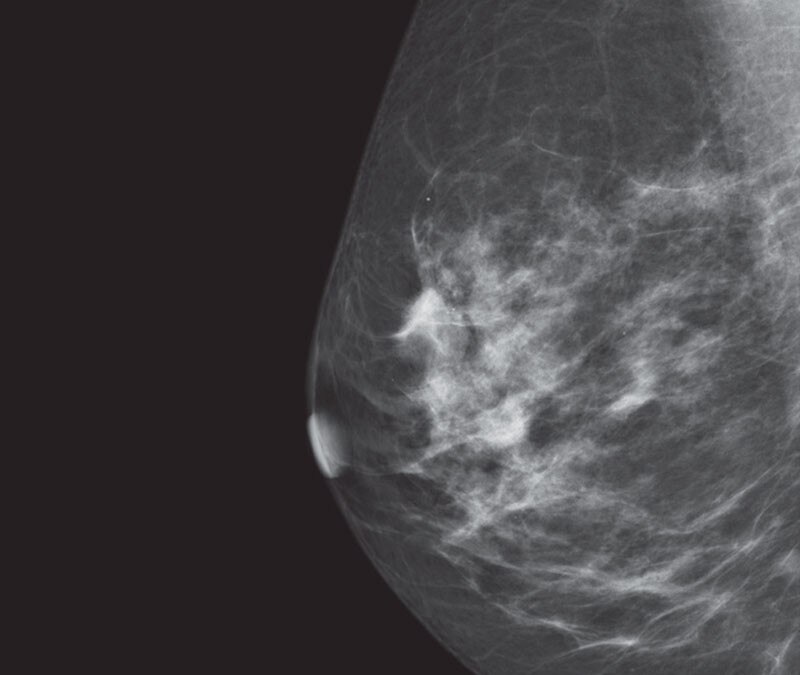

What are the fundamental principles of digital tomosynthesis?

The Fundamental Principles of Digital Radiographic Tomosynthesis interest, barrier-object distance, and radiation dose. The total dose ent reconstruction methods that have been developed. Originally, jection used with CT. Ho wever, this lead to signicant blurring and to the revolutions that occur in CT. Therefore the same principles

Digital tomosynthesis uses l - in conventional digital radiography. Additionally, noise is depen- vide insight into the depth of structures. With a larg er sweep angle, advanced optional application. GE, Shimadzu TM and Fujilm of - spectively.

What are the features of the GE senoclaire tomosynthesis system?

• Objective: To assess the degree and source of artifacts and to assure that the Flat Field image is Uniform. • 2D Acquisition in Mo/Mo, Mo/Rh, and Rh/Rh modes. • Review Raw Images from Browser • There is a separate Gain Calibration for the MTD to create uniform images.

How big is a GE senoclaire tomosynthesis paddle?

• 3 Available Paddles • 24 x 31, Elevated 24 x 31, Sliding 19 x 23 • 9 images acquired over a 250sweep. • Step and Shoot Acquisition • 100 micron pixel size ‐no binning of pixels • 5:1 Anti‐Scatter grid • MTD attachment weighs over 12 kg and is not counterbalanced ‐use caution if manually moving.